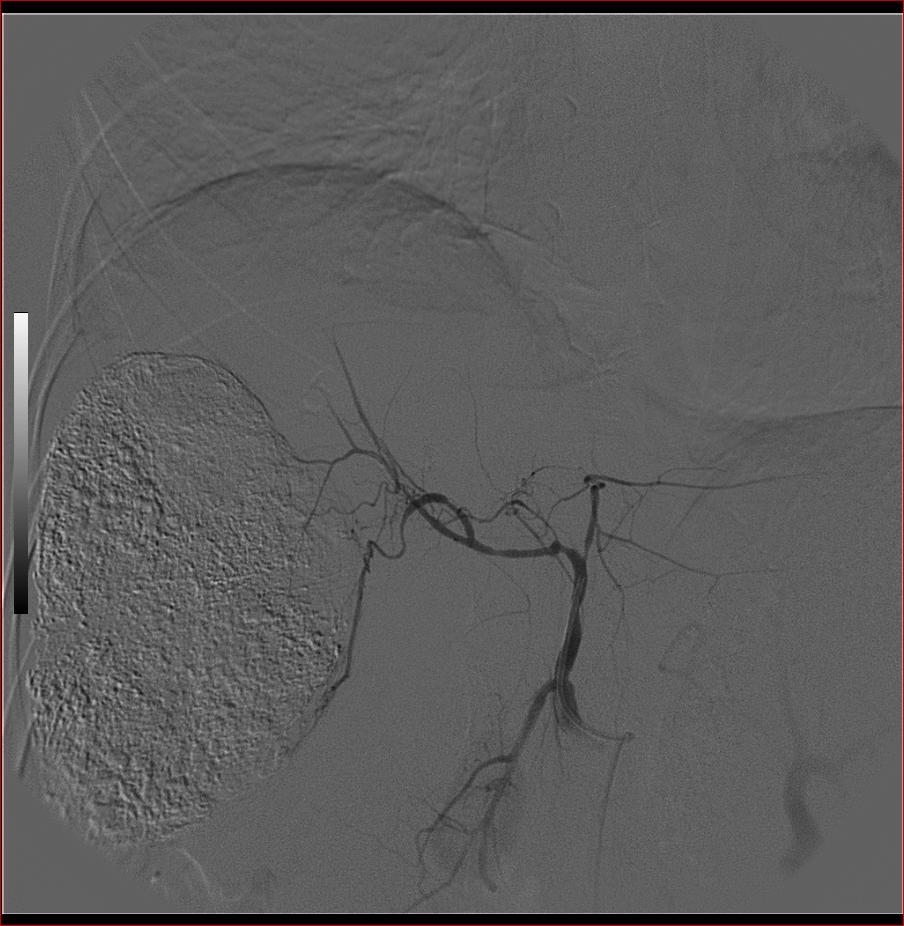

标题: DSA0138:F38Y,肝脏病变

第一次:

好牛的,右肝动脉发自肠系膜上动脉,不用微导管分次进行末梢栓塞,肿瘤染色完整。再次学习了。